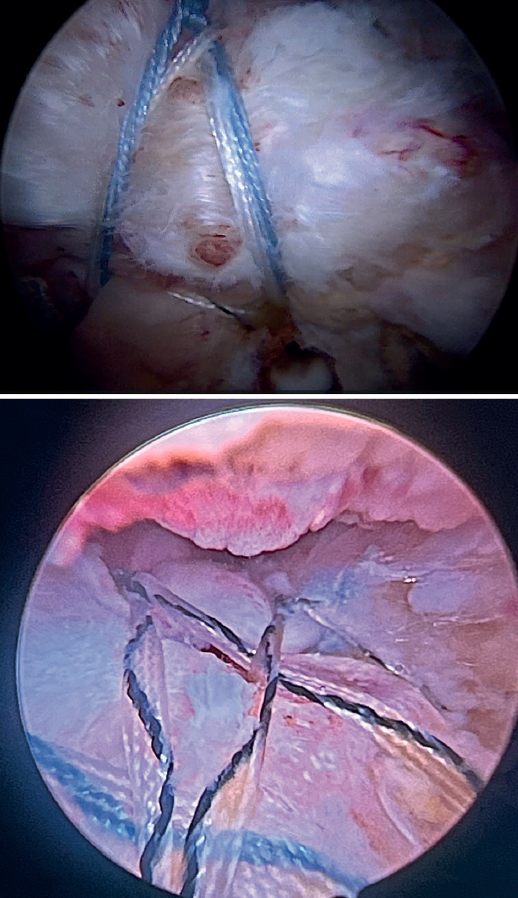

Using penetrating forceps through the anterior portal, the surgeon penetrates the LPB and retrieves one of the suture threads, performing a self-locking Lasso suture in the same step. This is done with two of the three anchoring threads to ensure a correct LPB grip to the footprint of the greater tuberosity and that the tendon does not fray; we do not cut the two threads after knotting (Figures 4, 5 and 6). We also consider it very important to apply the biceps tendon, keeping it as flat and anatomical as possible, avoiding twisting or excessive distension of the tendon. Subsequently, a tenotomy of the LPB distal to these sutures is performed (Figure 7), thus allowing the LPB to function as a superior capsular reconstruction, restricting the ascent of the humeral head.